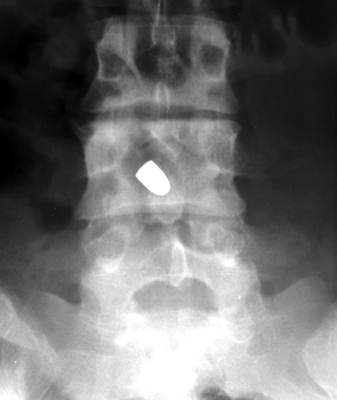

Tumbling Bullet Sign

Post traumatic bone cyst

Two sets of frontal and lateral radiographs, separated only by time, which reveal the "tumbling bullet sign"--which is simply a bullet which changes its location and orientation within a solitary bone cyst. This sign serves two purposes. It is documentation of the evolution of a solitary bone cyst as a corollary of trauma, and reveals the free movement of the foreign body within the confines of the lesion establishing its cystic rather than solid nature. It is similar to the fallen fragment sign.

- Click on the image for a larger versionA - Click on the image for a larger versionB - Click on the image for a larger versionC - Click on the image for a larger versionD

bulletTaxin RN, Feldman R.: The tumbling bullet sign in a post-traumatic bone cyst. Am J Roentgenol Radium Ther Nucl Med 1975 Jan;123(1):140-3.          [See related articles]